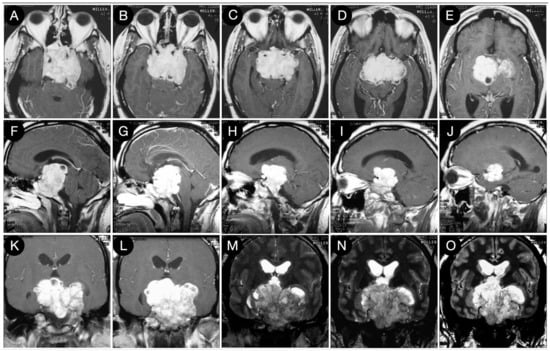

Case #1: Infradiaphragmantic Tumor with Middle Fossa Involvement through the Cavernous Sinus

3.2.1. Case #2: Involvement of the Anterior Skull Base

3.2.2. Case #3: Paramedian Pattern of Growth with Parenchymal Invasion

3.3.1. Case #4: Involvement of the Middle Skull Base with Parenchymal Invasion

3.3.2. Case #5: Extension beyond the Lateral Wall of the Cavernous Sinus

3.3.3. Case #6: Encasement of the Posterior Communicating and Anterior Choroidal Artery

Case #7: Encasement of the Paraclinoid and Supraclinoid Internal Carotid Artery

Case #8: Aggressive ACTH Tumor with Multiple Recurrences